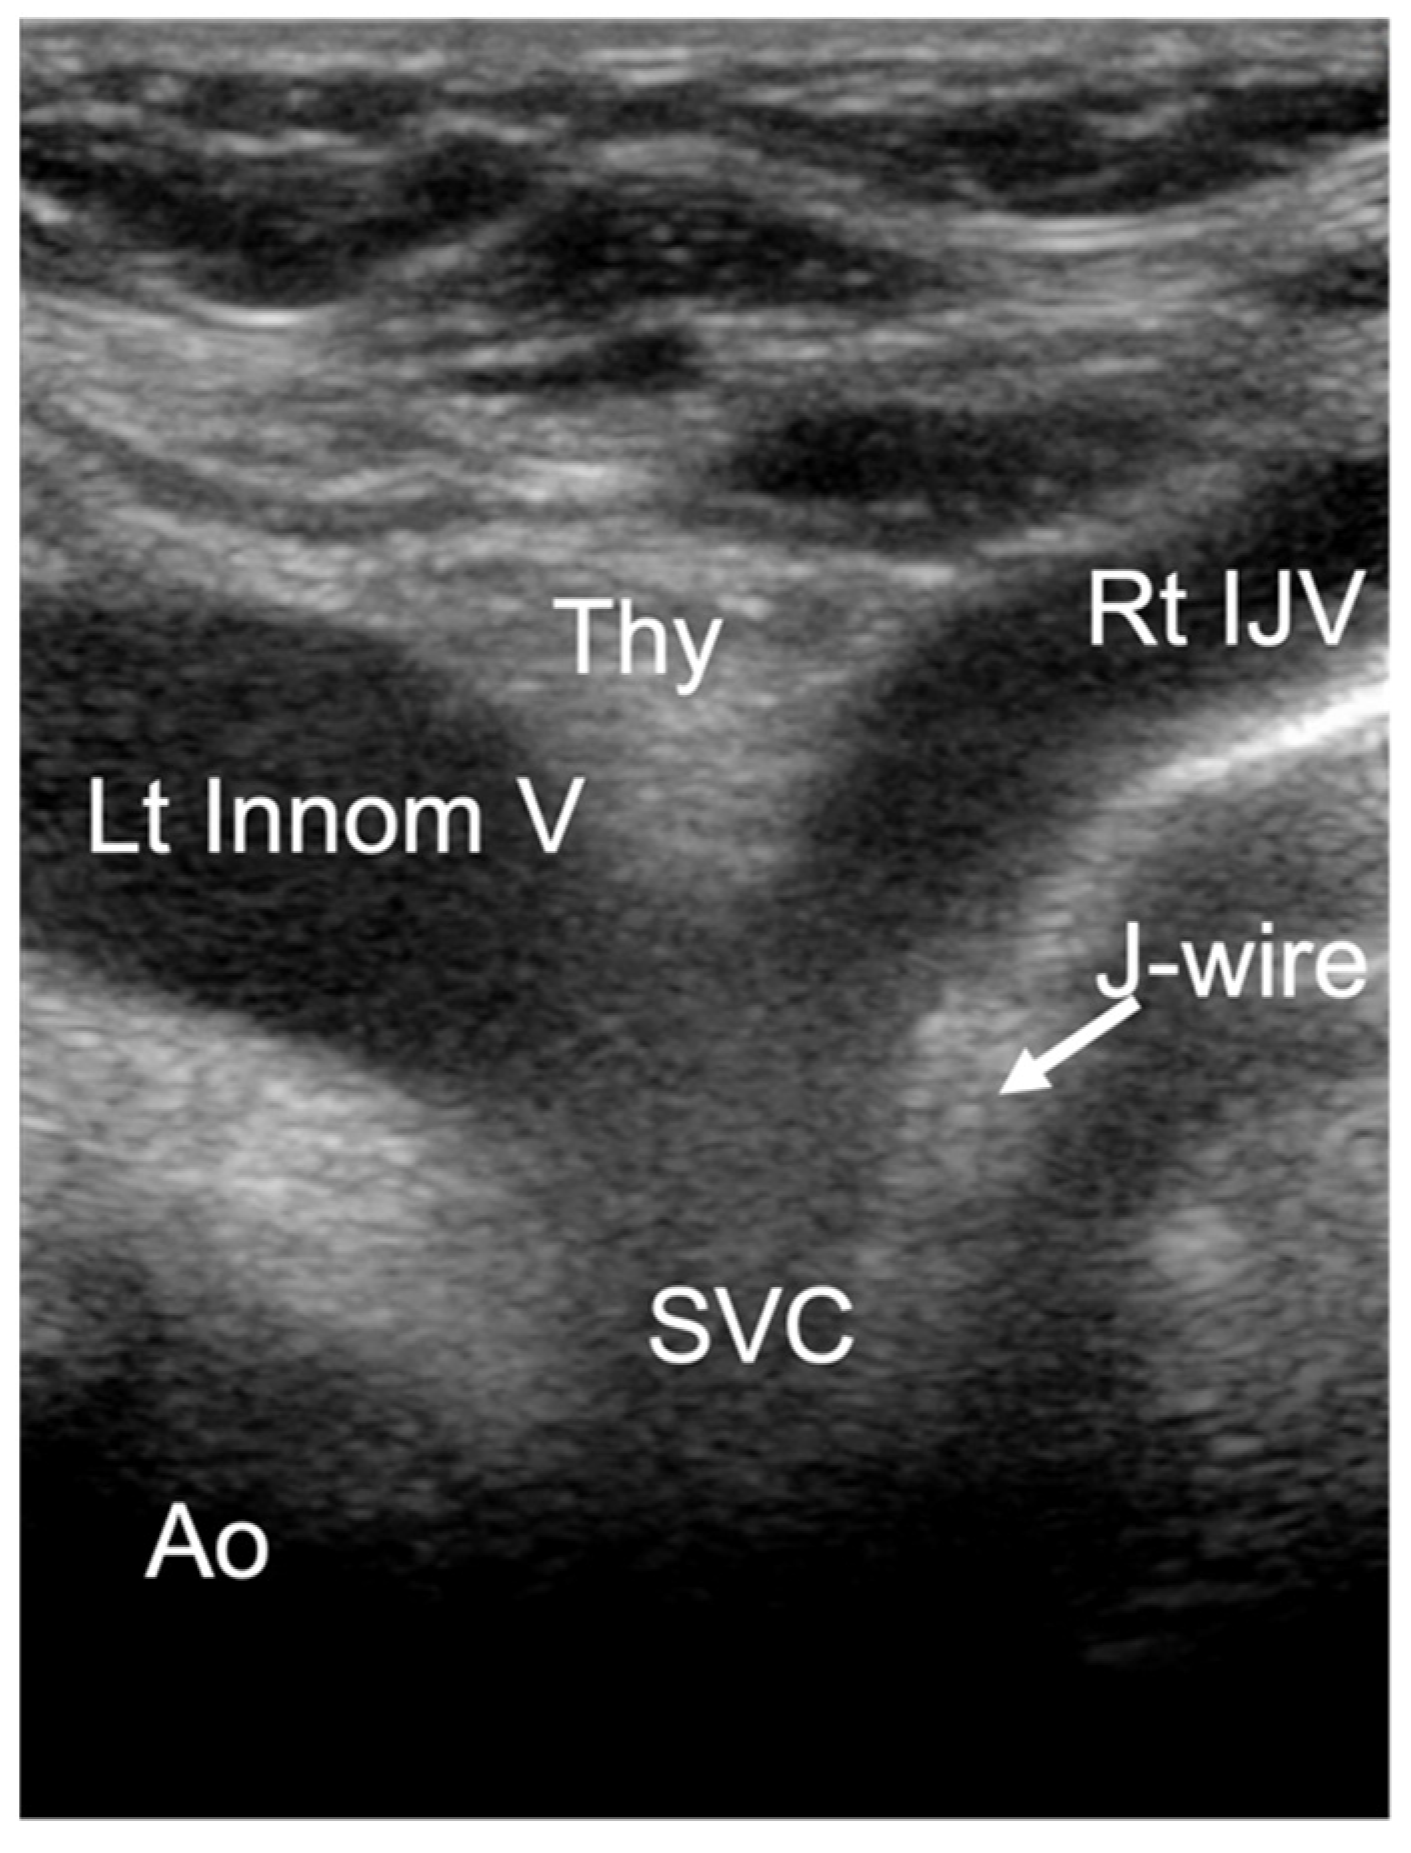

• Third view: suprasternal notch view

A cardiac sector transducer was primarily used. The use of a linear transducer/hockey stick is also possible in young children. The limiting factor is the penetration depth of the linear transducer or hockey stick. The connection from the right internal jugular vein to the innominate vein (Innom V) can be seen. Ideally, the junction into the right atrium and the distal ascending aorta in the cross-section are also visualized (Figure 4).

The CVC is identified by visualizing a double structure in the vein. The tip of the CVC is particularly echogenic. If the identification of the CVC tip is not clear, a useful tool is continuous flushing of the CVC with saline. Due to the small diameter of the CVC, a turbulent flow is created at the CVC tip, so that a clearly visible jet is created even without the use of agitated saline or ultrasound contrast medium (see Video S1). The jet is easy to identify and provides an indirect indicator of the position of the CVC. In addition, it is often possible to identify the J-wire of the CVC passing over the tip of the CVC (Figure 8).

Figure 4. Suprasternal notch view: superior vena cava (SVC), right internal jugular vein (Rt IJV), left innominate vein (Lt Innom V), aorta (Ao), thymus (Thy).